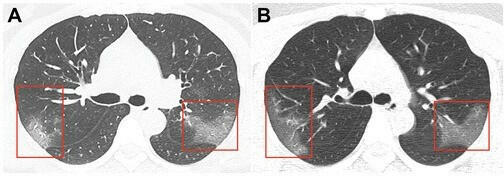

Jurnalda dərc edilmiş təsvirlər Çinin Lançjou şəhərində 39 dərəcə temperaturla xəstəxanaya yerləşdirilmiş 33 yaşlı qadının kompüter tomoqrafiyası nəticəsində alınıb.

Birinci şəkildə "tutqun şüşə effekti”ni yaradan bulanıqlıq görünür. Üç gün sonra çəkilmiş ikinci şəkildə isə virusun genişlənmiş sahəsini görmək mümkündür.